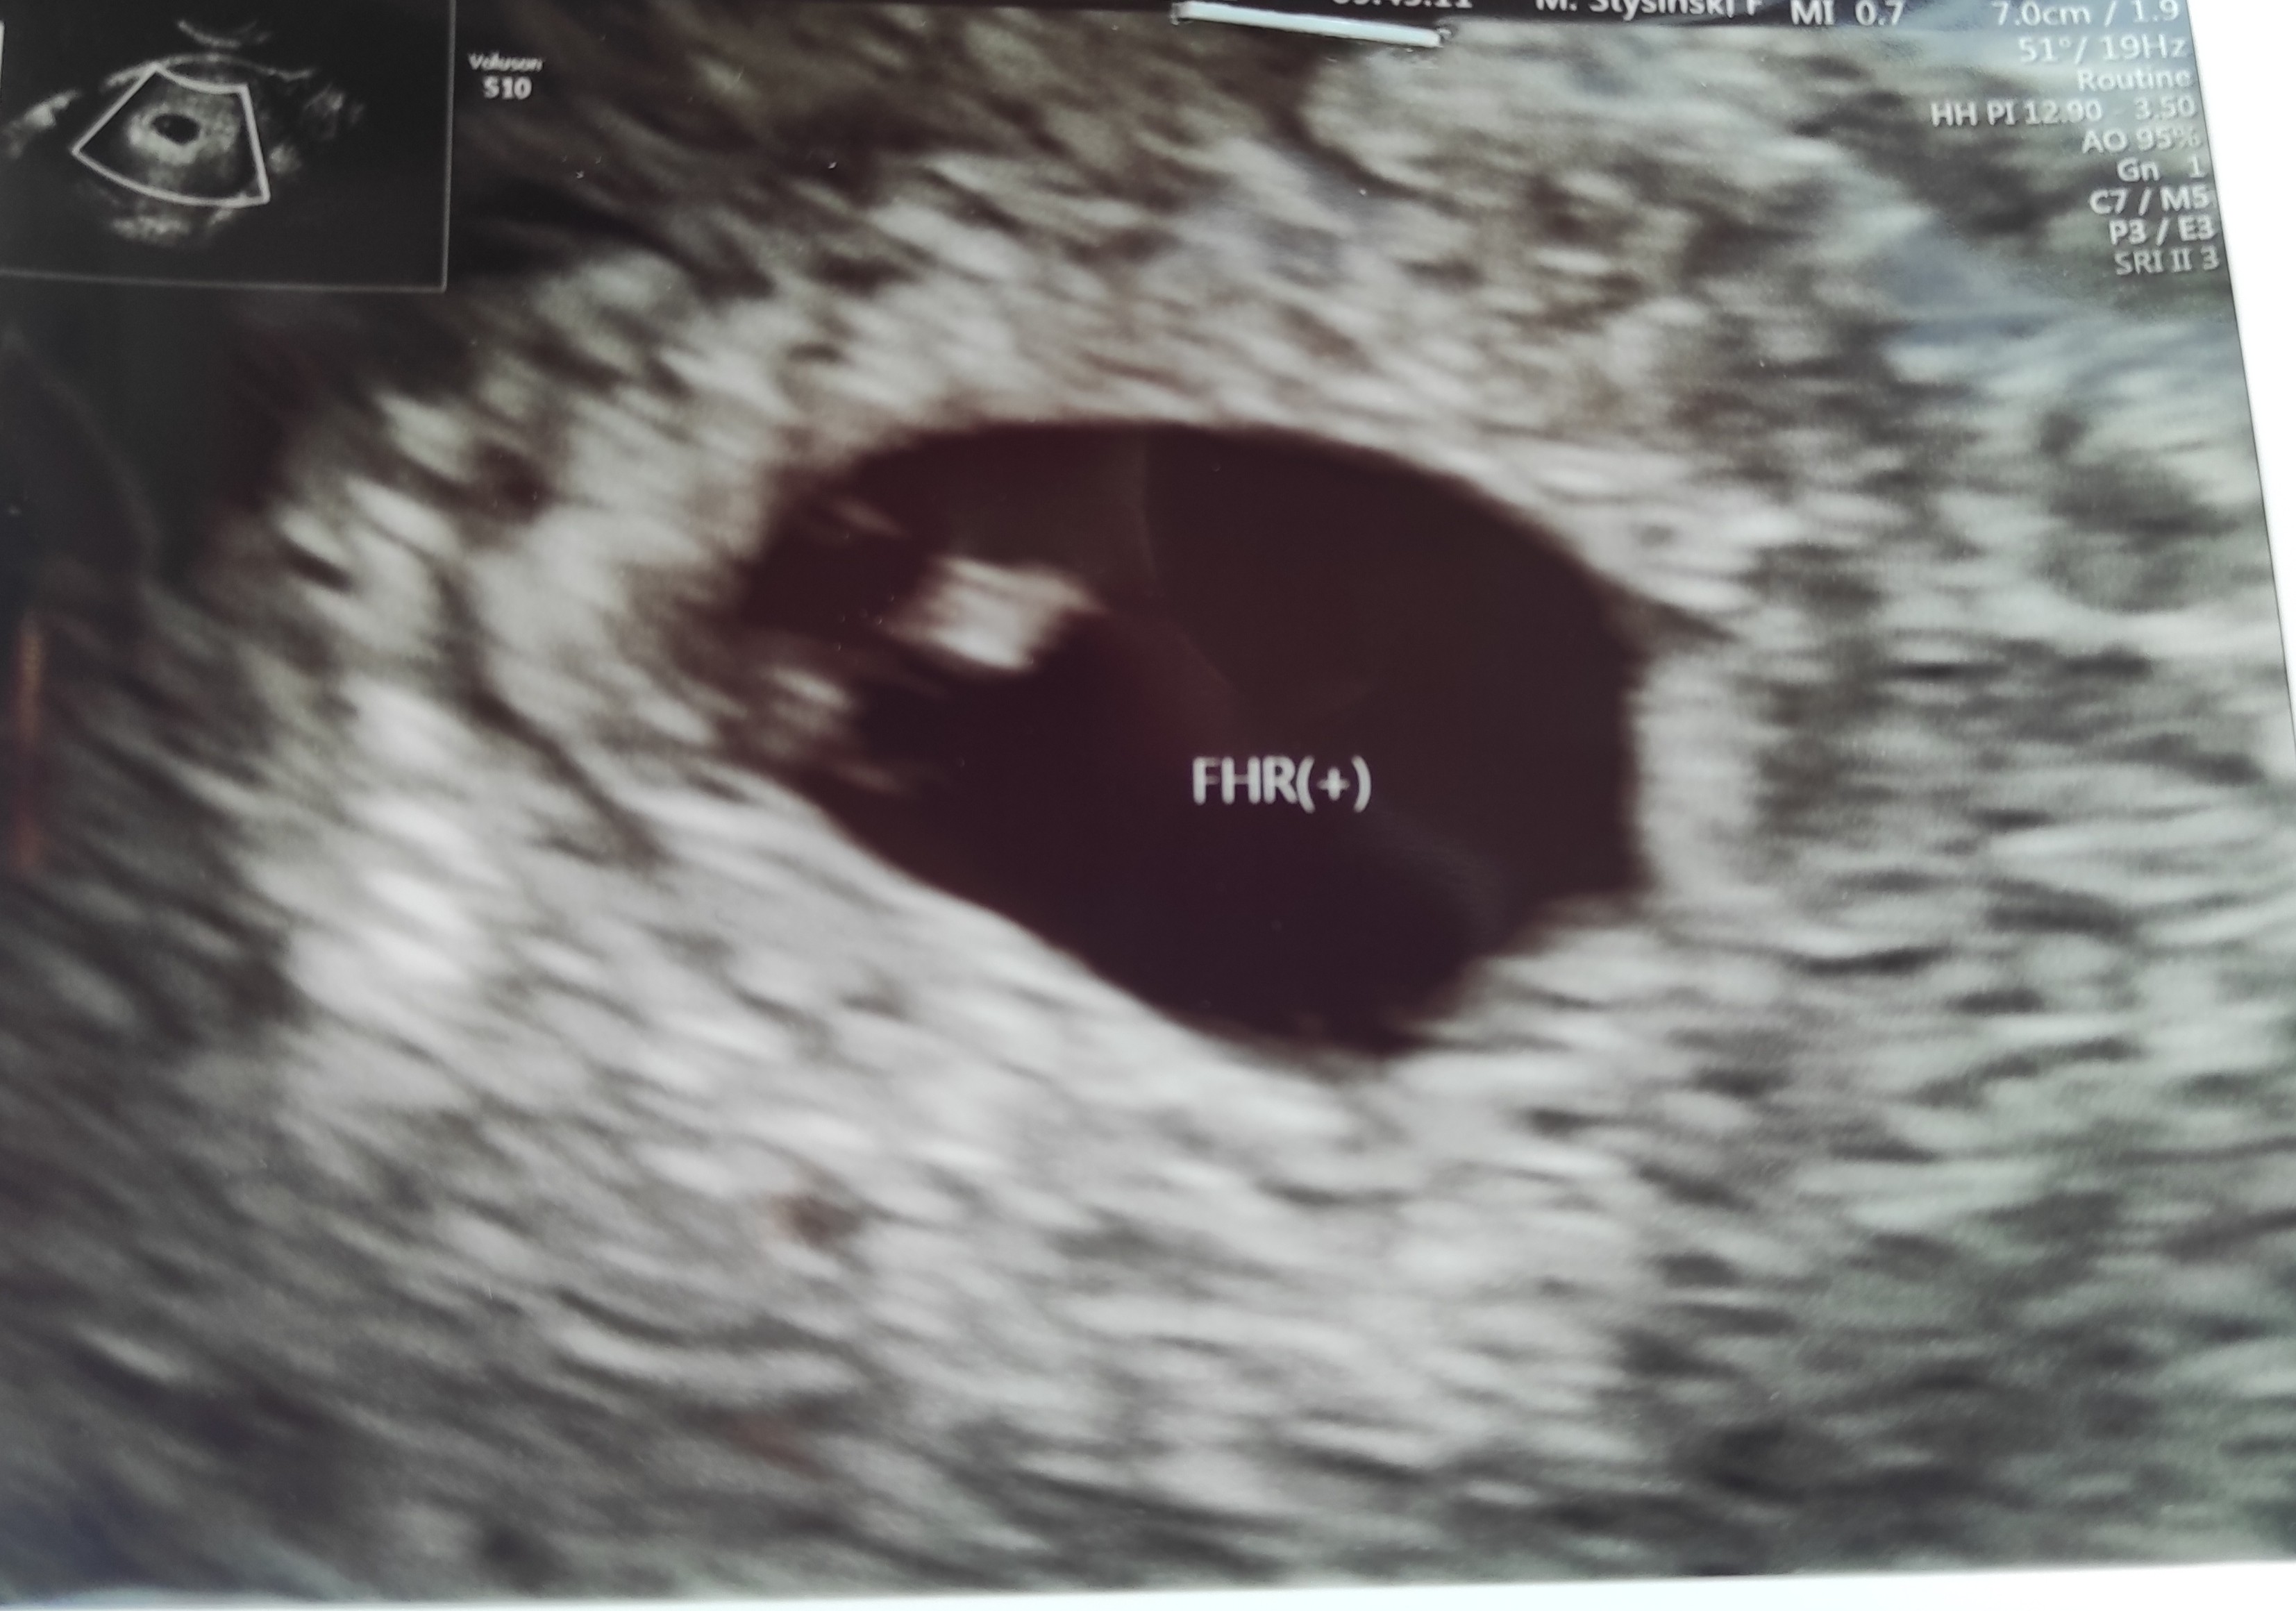

Chciałabym do Was dołączyć. Dziś byłam na pierwszej wizycie u ginekologa prywatnie - widać prawidłowo położony zarodek, ciałko żółte i pracę serca 🙂 wg opisu 5 + 6 dni. Termin 09.02. kolejną wizytę mam 29.07 i będę wtedy mieć badania prenatalne ( USG + PAPPA).

Chciałabym do Was dołączyć. Dziś byłam na pierwszej wizycie u ginekologa prywatnie - widać prawidłowo położony zarodek, ciałko żółte i pracę serca [emoji846] wg opisu 5 + 6 dni. Termin 09.02. kolejną wizytę mam 29.07 i będę wtedy mieć badania prenatalne ( USG + PAPPA).

Chyba na zdjęciu słabo widać ale na wizycie lekarz pokazał mi gdzie jest ciałko żółte, zarodek i bicie serduszka

Załączniki

• IMG_20210621_114834.jpg

IMG_20210621_114834.jpg

762,4 KB · Wyświetleń: 88